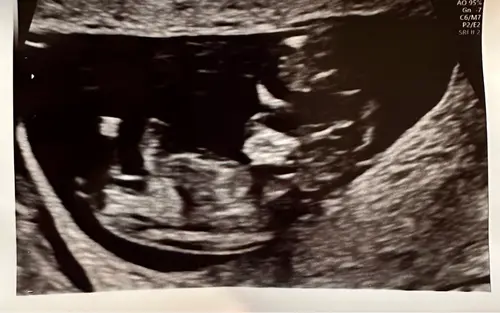

Iemand die een gokje durft te wagen? Deze echo is van precies 11 weken zwangerschap. De vk heeft er een duidelijke foto van de nub bij gedaan, zodat we zelf konden puzzelen haha. Ben benieuwd wat jullie denken! 🩵🩷

Iemand enig idee? De vk zei dat ze (maar totaal nog niet betrouwbaar) dacht dat het weer een jongetje zou worden😊 Ben nu precies 11 weken.

Nub is dat witte streepje helemaal rechts. Ik vind de foto net niet duidelijk. De stand is namelijk meisje (maar zo staan ze tot 12 weken dus allemaal) maar het uiteinde lijkt wel iets weg te hebben van een jochie.

Dat bovenste witte streepje rechts is volgens mij de nub. Staat in meisjes-stand maar dit hebben ze tot 12 weken bijna allemaal. Zie dat je 11 weken bent, misschien ben je net te vroeg